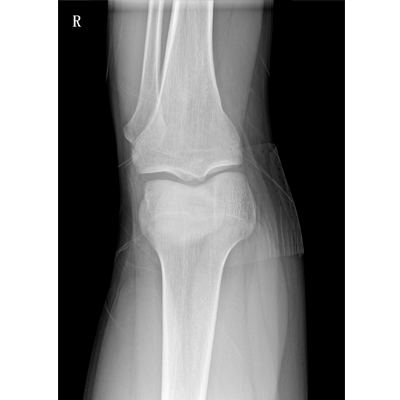

輕量化設(shè)計(jì) 小巧靈活 PLX5100

用于影像科、急診室、病房、ICU、手術(shù)室等多場(chǎng)景應(yīng)用。

● 數(shù)字化無線平板成像,操作簡(jiǎn)便,成像質(zhì)量高